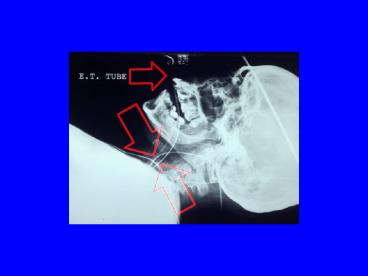

How to provide advanced airway management?

• Lost Resident Surgical Cover

• Loss of Anaesthetic Cover